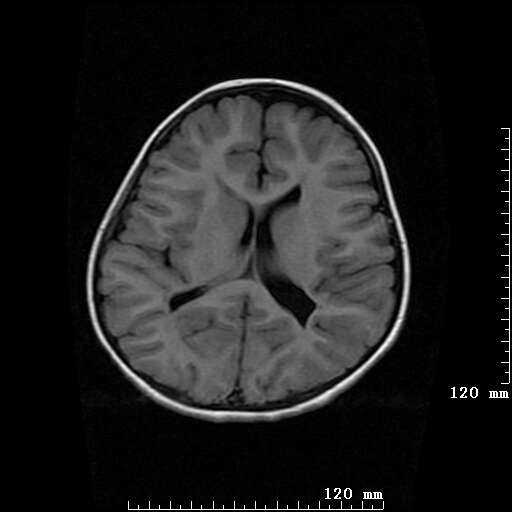

女,7岁,三岁才说话、走路。现智力尚可,走路不稳。临床怀疑大脑发育不全。

考虑 脑白质发育不良

脑折质变薄,双侧侧脑室稍扩张,支持考虑脑折质发育不良

侧脑室周围白质软化症。

考虑胼胝体发育不全,髓鞘形成不良。

支持考虑胼胝体发育不全,髓鞘形成不良。

脑裂畸形伴灰质异位

侧脑室周围白质数量减少,侧脑室不对称性扩大,左侧侧脑室后角呈方形改变,脑沟加深,结合临床考虑脑室周围白质软化症(pvl)。期待结果!

只看出灰质异位

支持脑白质发育不良。